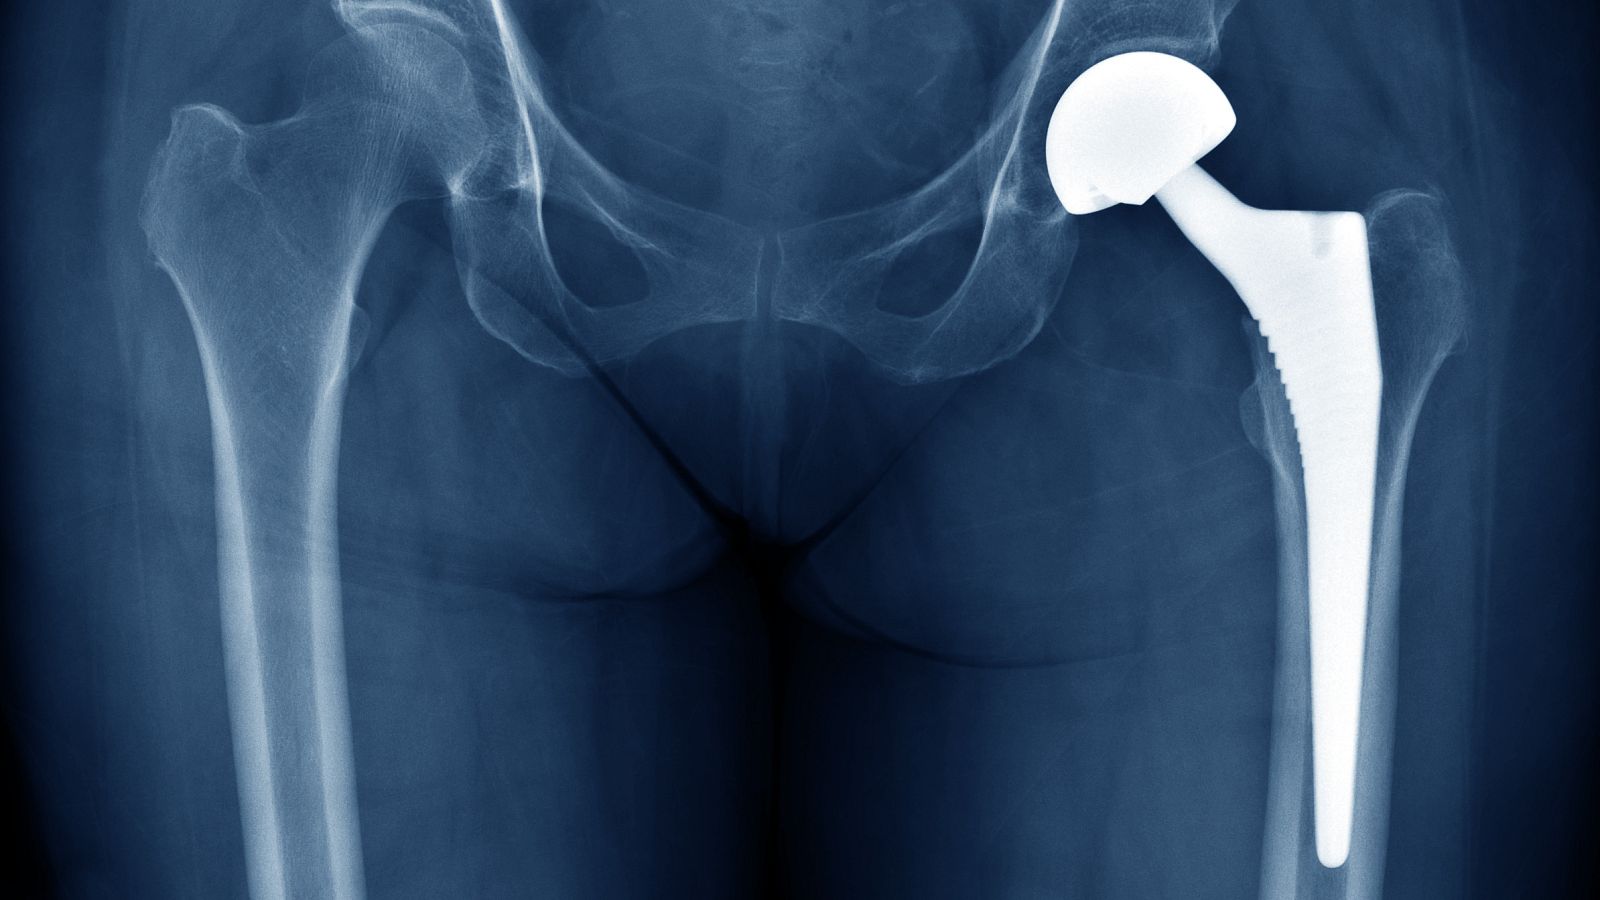

La Audiencia Nacional investiga a Johnson & Johnson por prótesis de cadera defectuosas

La Audiencia Nacional está investigando a la farmacéutica estadounidense Johnson & Johnson por comercializar presuntamente prótesis de cadera defectuosas que han sido implantadas en varios países, entre ellos España, donde hay 1.471 afectados.

Las prótesis, que dejaron de implantarse hace nueve años por riesgo para la salud de los enfermos, se distribuyeron en 70 hospitales, ha asegurado a EFE el abogado de los demandantes españoles, Emilio Ortiz.

El problema observado, según señalaba la agencia española en esa alerta, era "el aumento del número de aflojamientos detectados a los cinco de años de implantadas estas prótesis" y el posible desprendimiento de "restos metálicos de la aleación cromo-cobalto a los tejidos circundantes a la prótesis que pueden causar dolor o inflamación".